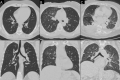

Figures